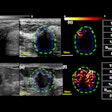

The sonographic images were of the right upper quadrant, subxiphoid, left upper quadrant, bladder, aorta, and right lung, as well as right internal jugular vein views to verify central line insertion.

A total of 189 images were obtained from 27 exams. The images were evaluated by two blinded emergency sonographers who were certified in ultrasound image interpretation, along with a board-certified radiologist. Each was asked to assess and rank both image quality and clinical utility on a scale of 1 to 10.

Session presenter Dr. Davut Savaser, an attending ED physician and a clinical instructor in emergency medicine, said that all 189 images received a score of 8 or higher by all reviewers. The hand sanitizer scored the best, at a median of 9.2, followed by the hairstyling gel and olive oil at 8.9. The images acquired with ultrasound gel were rated at 9.6.